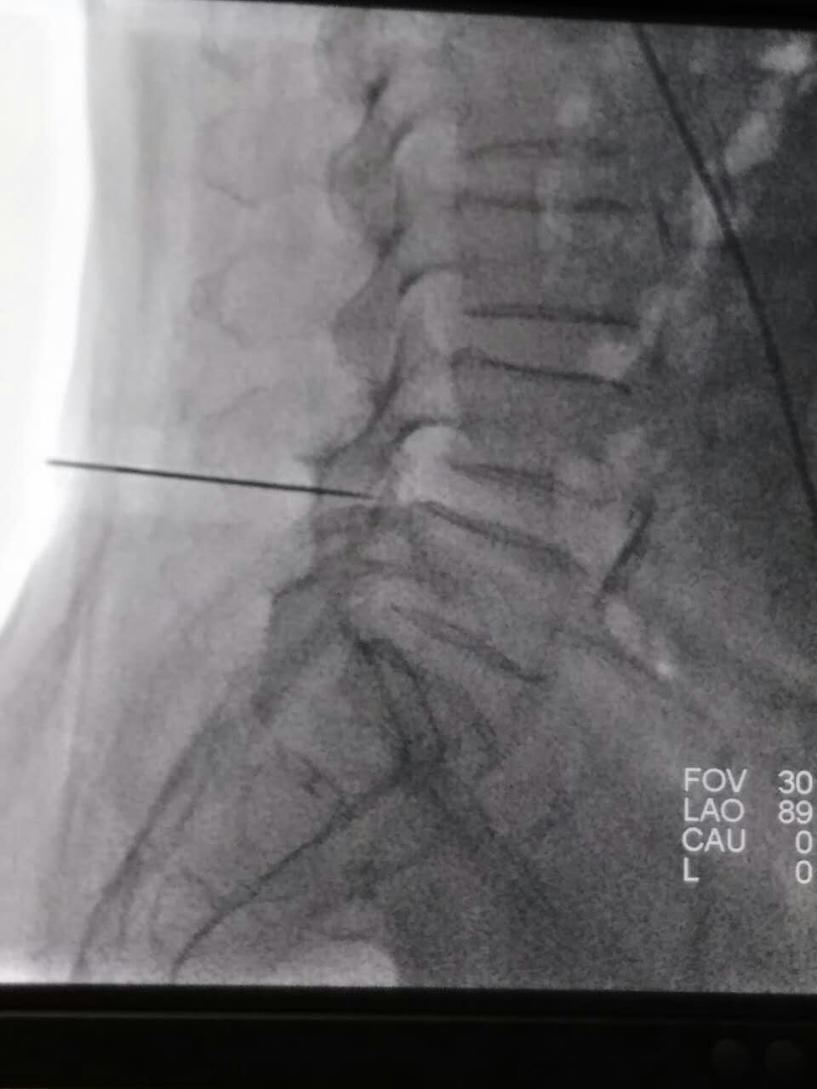

术中,为了定位透照期间为了防避免老人害怕和随时监测,我们团队的杨大夫穿上铅衣陪同老人。由于准备充分,配合给力,手术也异常顺利,半个小时结束。术后的当天中午患者就能和家属坐起来一起吃饭了,家属说这是几个月来的第一次。第二天老人就推着轮椅可以走个不停。前些天我们随访,患者的儿子说:“老人现在每天都下楼两趟溜溜弯。以前,担心老人下不了床;现在,我们担心老人走丢了。”

腰椎管狭窄症,典型的表现就是“间歇性跛行”:走个几十米就出现大腿酸困、麻木和疼痛,强挺着走起来就像瘸了似的,这个时候坐下来歇一会儿,还能走,不过走的会越来越近了。但是这类患者在坐位、骑自行车等会没有什么障碍。我们军工医院疼痛科在查阅文献找寻病因和以往针刀治疗的基础上,进行针刀韧带松解等系列贯序疗法来增大椎管容积、消除椎管内粘连、减小腰背筋膜张力等,从而使腰椎管狭窄症患者的临床症状大大缓解。对于影响生活质量、不愿意或不适合开放椎管减压的患者尤为适合。

对腰椎管狭窄症的关注和影像引导下针刀韧带松解技术的开展,让我们医生多了一种精准微创治疗手段,同时患者也多了一些缓解病痛的希望。